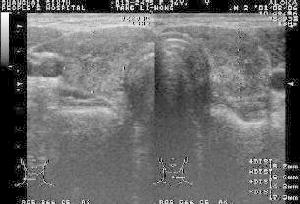

緩慢進展的堅硬甲狀腺腫,向周圍組織浸潤應考慮慢性侵襲性纖維性甲狀腺炎。確診主要依賴甲狀腺病理檢查。